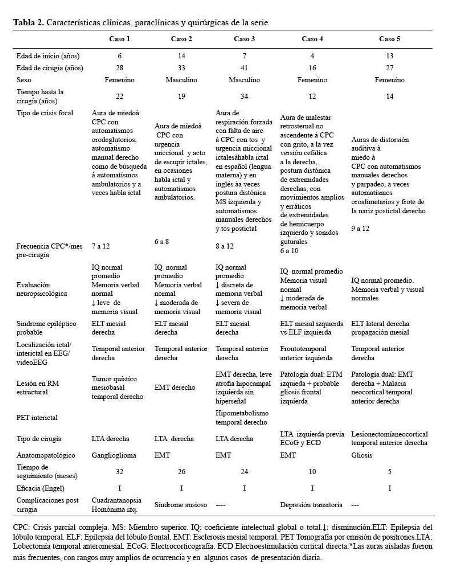

En nuestra base de datos encontramos 8 pacientes con epilepsia refractaria intervenidos quirúrgicamente en los 4 últimos años. Sin embargo, para propósito de este reporte excluimos a tres pacientes, 2 pacientes son Síndrome de Lennox Gastaut operados de callosostomía, el más antiguo data de hace 4 años; y una paciente con epilepsia multifocal por esclerosis tuberosa a quien se le colocó estimulador del nervio vago. Se analizaron, por tanto, los resultados de 5 pacientes (3 mujeres y 2 varones), con una edad promedio de 29 años (16 -41 años). La edad media de inicio de la epilepsia fue de 8,8 años (4–14 años). El tiempo de evolución de la epilepsia al momento de la cirugía fue en promedio de 20,2 años (12 -34 años). Las características semiológicas, paraclínicas y quirúrgicas se resumen en la tabla 2.

De los 5 casos, 3 cirugías correspondieron a pacientes con epilepsia temporal mesial derecha (2 por esclerosis mesial temporal y 1 por ganglioglioma mediobasal temporal anterior) y 2 correspondieron a patología dual (1 con EMT derecha más lesión gliótica cicatrizal de un angioma cavernoso temporal neocorical ipsilateral operado previamente y 1 con EMT izquierda más gliosis frontal ipsilateral). De los 3 pacientes con epilepsia temporal mesial derecha, 2 sólo requirieron de estudios paraclínicos en fase 1: EEG/VideoEEG y RM encéfalo estructural y 1 requirió además de PET interictal (fase 2), pues a pesar de que la semiología y actividad electrográfica ictal correspondían a una epilepsia del lóbulo temporal mesial derecho, la RM de encéfalo dejaba duda respecto a si además de tener EMT derecha,tenía también EMT izquierda. A estos tres pacientes se les realizó lobectomía temporal anteromesial (LTA) que incluyó amigdalohipocampectomía, siguiendo las técnicas quirúrgicas del Programa de Epilepsia del London Health Sciences Centre, University of Western Ontario, Canadá (20). Las 2 pacientes con patología dual fueron intervenidas con el apoyo de electrocorticografía (ECoG) aguda o intraoperatoria. En una de ellas se demostró que la lesión frontal izquierda ipsilateral era silente, no se resecó y se realizó solo LTA izquierda. En la otra paciente, la ECoG orientó a realizar una lesionectomía ampliada de la lesión neocortical temporal anterior; pero tuvimos que abstenernos de realizar una amgdalohipocampectomía a pesar de tratarse de una patología dual, pues su reserva cognitiva y la memoria, tanto verbal como visual estaban indemnes. Es importante señalar que en ésta paciente la semiología ictal inicial era neocortical (auras auditivas, seguidas solo después de segundos de miedo). En la primera paciente con patología dual además se realizó estimulación cortical directa para la evaluación intraoperatoria del lenguaje con la paciente despierta; se puede revisar en detalle el procedimiento en un reporte del caso publicado previamente (21). No se realizaron en esta serie resecciones extratemporales. Los resultados de anatomopatología evidenciaron como etiología definitiva: 3 EMT, 1 ganglioglioma y 1 gliosis reactiva; esta última corresponde a la paciente con patología dual con lesión gliótica cicatrizal neocortical temporal derecha, operada en años previos de angioma cavernoso en dicha zona. Las imágenes de RM de encéfalo y EEG de los casos 1, 2, 3 y 5 pueden ser revisadas en la figura 1,figura 2,figura 3 y figura 4 Las imágenes del caso 4 pueden ser revisadas en un reporte de caso publicado previamente (21).

El tiempo de seguimiento fluctuó entre 5 a 32 meses, con una media de 19,4 meses.Los resultados de eficacia quirúrgica fueron de libertad de crisis (Engel I) en los 5 pacientes al término de seguimiento. Cabe mencionar que la paciente 1, a los 18 meses de la cirugía planificaba gestación y por cuenta propia redujo gradualmente su medicación: Carbamazepina 1200 mg/ día a 200 mg/día y luego de 3 semanas presentó auras de miedo menores a 30 segundos sin otra fenomenología, 2 a 3 veces/semana por 2 semanas no siendo incapacitantes; se logró revertir tal situación al instaurar tratamiento antiepiléptico con Levetiracetam 2 g/día con titulación rápida (la paciente no aceptó retomar su medicación habitual) y luego de ello no han recurrido crisis. Así mismo la paciente 5 presentó en la primera semana postquirúrgica, 4 auras auditivas seguidas de miedo sin compromiso de conciencia y no incapacitantes,pero luego y hasta la fecha quedó libre de crisis. Excepto la paciente 1, los otros 4 pacientes han permanecido con su medicación antiepiléptica habitual hasta el final del seguimiento.

Respecto a las complicaciones postquirúrgicas, un paciente con LTA derecha desarrolló un síndrome ansioso y una paciente con LTA izquierda desarrolló un cuadro clínico compatible con síndrome depresivo;ambos, resueltos dentro del mes con inhibidores selectivos de recaptación de serotonina. Una paciente con LTA derecha presentó como secuela, cuadrantanopsia homónima superior izquierda con mejoría parcial, siendo en la actualidad subclínica. No se registraron otros déficits neurológicos, variaciones significativas en las funciones neuropsicológicas medidas en las pruebas psicométricas postoperatorias, neuroinfecciones ni mortalidad asociada.